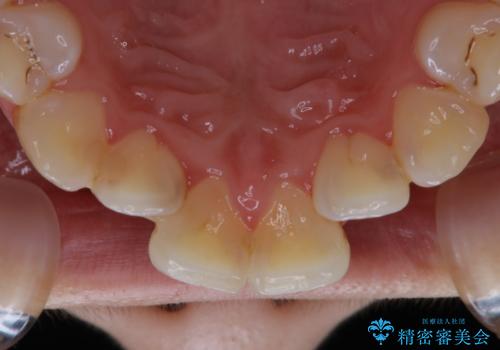

歯面がバイオフィルム(細菌の塊)や歯石で覆われていました。

PMTC(自費クリーニング)で、専門的な器具を使用し、歯石を砕き、バイオフィルムを剥がし、トリートメントまで行いました。歯肉が腫れていたため、バイオフィルムや歯石を取り除いたことにより、施術後の歯肉から出血が見られます。ただし、出血は次第におさまります。

PMTC(自費クリーニング)はホワイトニングではないため、歯が白くなることはありませんが、徹底的に汚れを除去しますので、ご自身本来の歯面となり、艶がでて明るい印象となります。